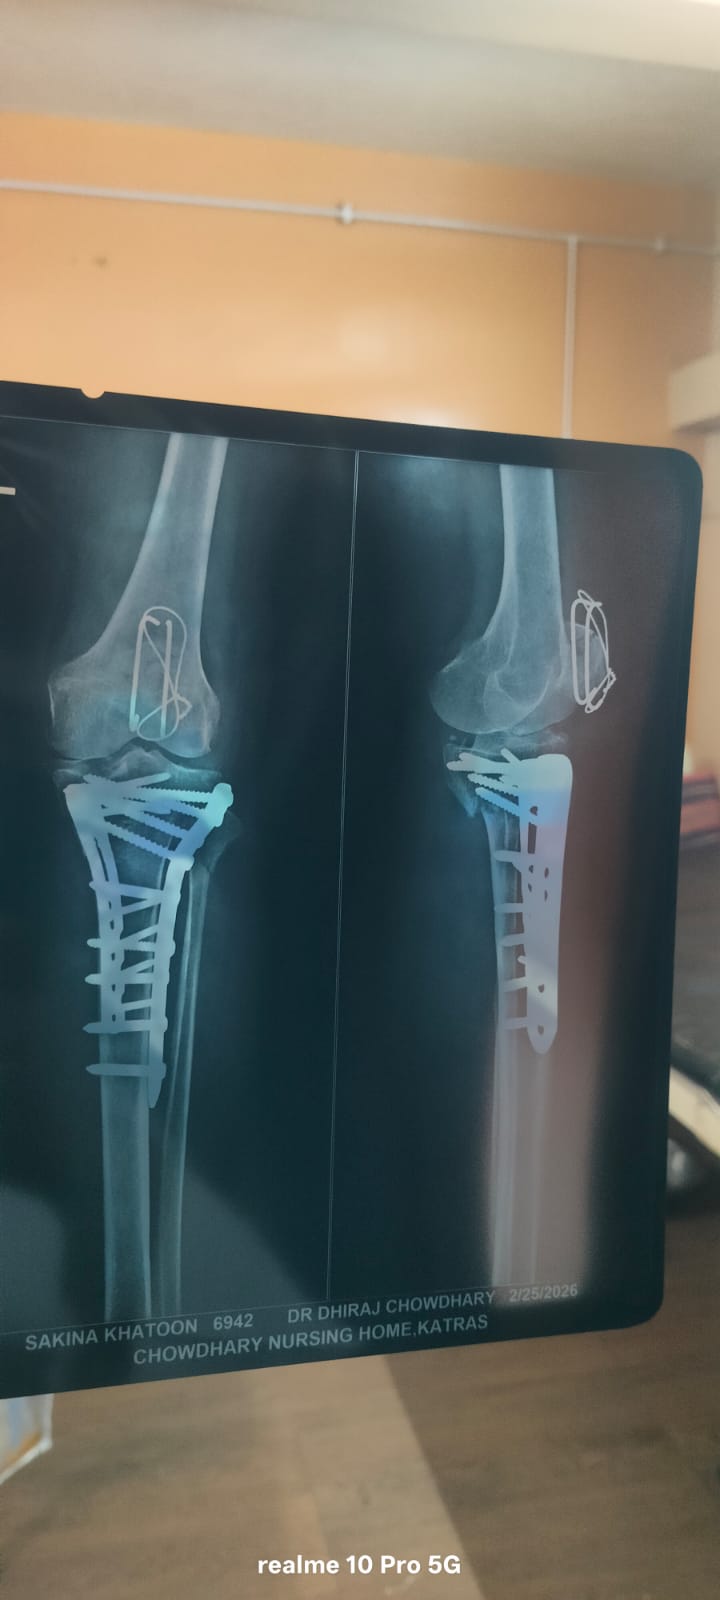

The Imam Sahab of a prominent masjid is currently going through a very difficult time. (Name withheld for obvious reasons.) His mother has suffered a serious fall from the terrace, resulting in fractures to two bones. She requires urgent surgery and medical care. We humbly request your kind support in helping to raise the necessary funds for her treatment.